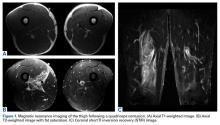

A quadriceps contusion is a clinical diagnosis based on a typical history and physical examination; therefore, advanced imaging usually does not need to be obtained except to gauge the severity of injury, to rule out concurrent injuries (ie, tendon rupture), and to identify the presence of a hematoma that may necessitate aspiration. Plain radiographs are typically unremarkable in the acute setting. Appearance on magnetic resonance imaging (MRI) varies by injury severity, with increased signal throughout the affected muscle belly and a diffuse, feathery appearance centered at the point of impact on short TI inversion recovery (STIR) and T2-weighted images reflecting edema and possibly hematoma (Figures 1A-1C).8,11